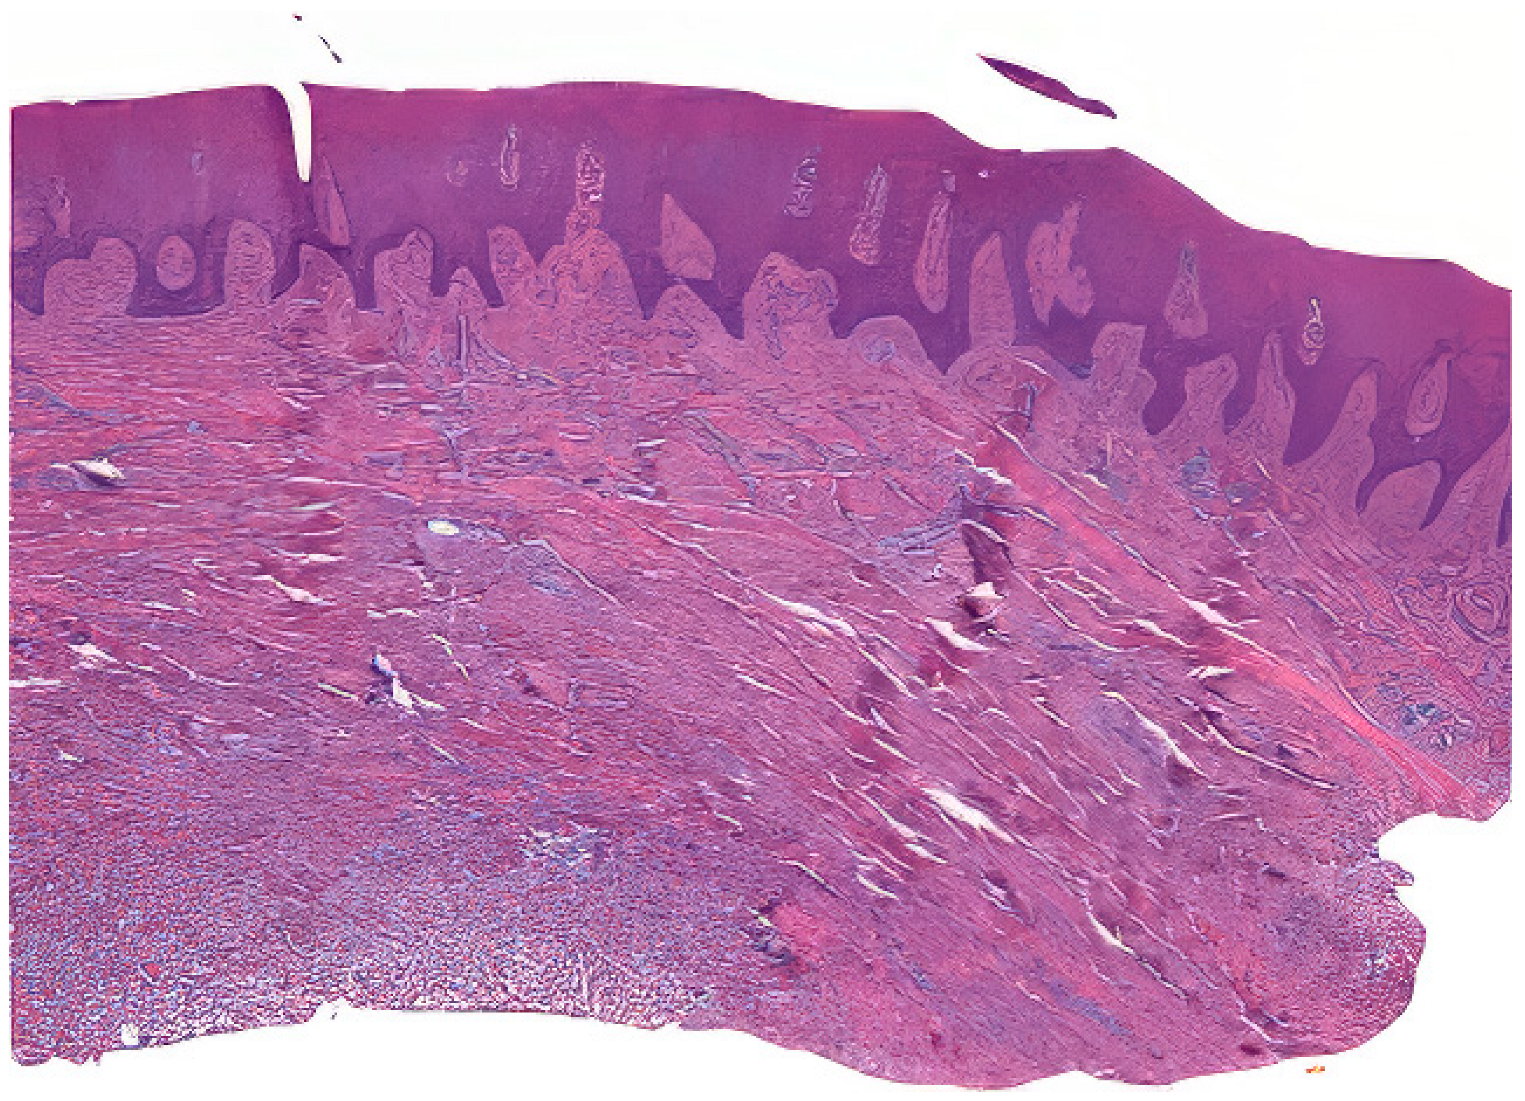

Tissue samples were collected from excess epithelial–connective graft material, which underwent shaping and finishing procedures during surgery. A total of 50 samples from 25 patients were fixed in Karnovsky’s solution (2% paraformaldehyde, 2.5% glutaraldehyde in 0.1 M sodium cacodylate buffer) for 6 h at 4 °C, followed by washing in 0.1 M cacodylate buffer with added sucrose. After fixation in Karnovsky’s solution, the tissue samples were washed in 0.1 M cacodylate buffer with added sucrose to remove excess fixative. The dehydration process involved immersing the samples in increasing concentrations of ethanol (70%, 80%, 90%, 95%, and 100%), followed by clearing in xylene. The cleared samples were then infiltrated with paraffin at 60 °C under vacuum conditions to ensure thorough embedding. Serial sections of the embedded tissue blocks were cut at 4–5 μm thickness using a rotary microtome Leica SM 2400 microtome (Leica Biosystems, Nußloch, Germany). The sections were mounted on glass slides and dried at 37 °C overnight. Hematoxylin and eosin staining was performed (Figure 2) [23].

The stained sections were observed under a Nikon Eclipse 600 (Minato, Tokyo, Giappone) microscope with a Nikon DS-U1 digital sight camera. Two blinded expert operators (AZ and MR) performed the histological and histomorphometric analyses. NIS-Elements software 4.5 version facilitated measurements at low magnification (20×), focusing on parameters such as epithelial height, total graft height, and perimeter (Table 1).

Figure 2. Example of a prepared sample.